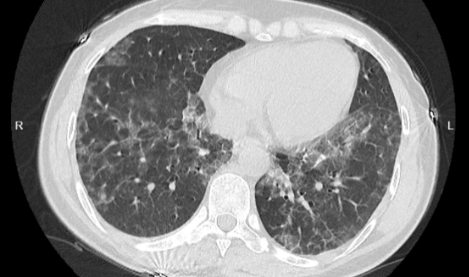

白肺是目前很常见的情况,受新冠影响很多老年人都出现了白肺的情况,当然也有年轻人会患上白肺。那么,如何自查是否出现白肺?平时怎样保护自己的肺?一起来看看中睿百科网带来的详细介绍吧!

如何自查是否出现白肺

如果出现白肺,患者可能会出现一些严重的呼吸道症状,包括咳嗽、喘息、呼吸困难或体力活动时呼吸短促。一个更客观的指标是病人的呼吸频率,通常大于每分钟30次呼吸,或血氧饱和度低于93%就要警惕出现严重肺部感染。白肺并不能预防,只能预警。

肺白了还能恢复吗

肺白了一般是指白肺,白肺能否恢复与疾病类型、严重程度有一定关系,有些患者在检查时,发现肺白密度增高,如果是轻度肺部炎症引起的白肺一般是可以恢复的,如果是严重肺部炎症或肺间质纤维化引起的,则可能无法恢复。

如果是比较严重的肺炎或肺间质纤维化引起的白肺,一般会伴有呼吸困难的症状,首先应该改善患者的呼吸状态,可以帮助患者通过吸氧呼吸,也应该使用抗生素类药物进行治疗,症状消退后,白肺症状会相应减轻,但一般不会完全恢复。

此外,白肺也可能由肺结核、肺肿瘤等原因引起,需要鉴别诊断。